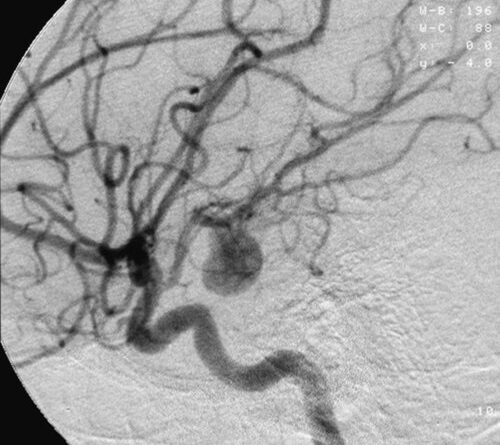

როდესაც ანევრიზმაზე ვსაუბრობთ საქმე თავის ტვინის მკვებავ არტერიებს ეხება – ვისაუბრებთ პროცესზე, რომელიც თავის ტვინის სისხლის მიმოქცევის სისტემაში მიმდინარეობს.